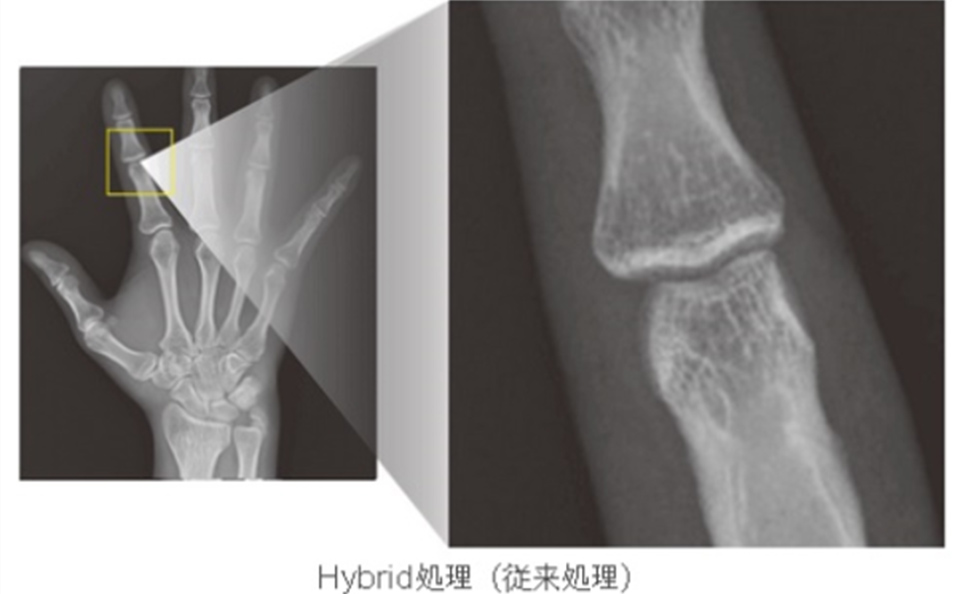

⼀般撮影部⾨

⼀般撮影部⾨は、胸部や腹部、また頭部から四肢などのX線撮影を⾏います。

当センターでは、FPD装置(フラットパネルディテクタ)の採⽤により、全⾯デジタル化が実現されております。

デジタル画像処理技術により、⾼解像度、⾼鮮鋭化の診断画像が提供でき、低被ばくでの撮影が可能となりました。